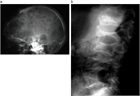

病態

1. 多発性骨髄腫は、B細胞の終末分化段階である形質細胞の単クローン性(腫瘍性)増殖を特徴とする疾患である。

1. 多段階発癌過程を経て、意義不明の単クローン性ガンマグロブリン血症(MGUS)より無症候性骨髄腫、症候性骨髄腫へと進展する。